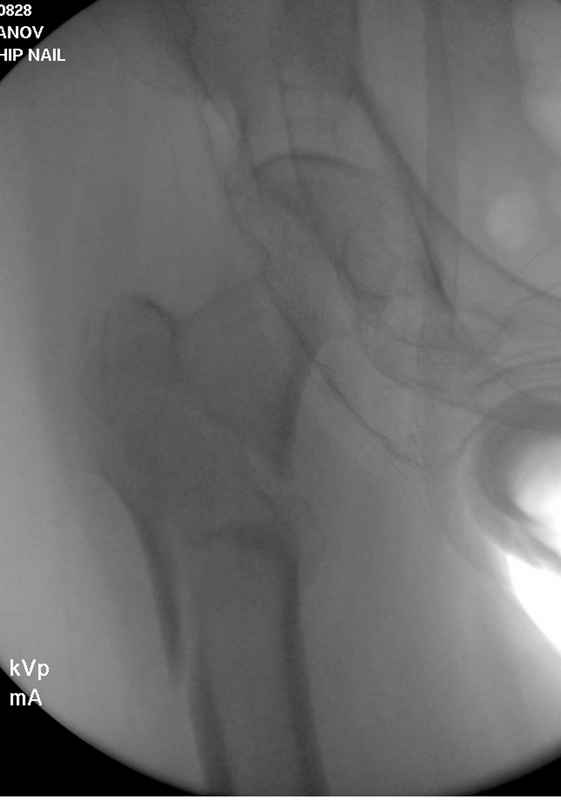

Здесь 83 года, травма в результате падения